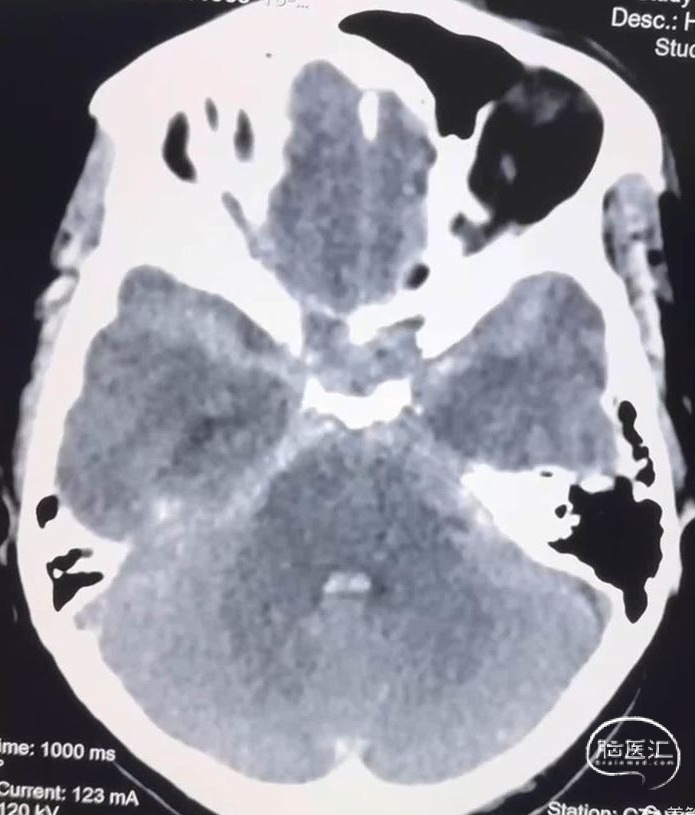

这是一个中年女性,广东佛山人,来青海旅游期间突然出现剧烈头痛、恶心、呕吐,由朋友送到距离最近的县医院,头颅CT示广泛性蛛网膜下腔出血,遂快速转入我院进入绿色通道进行快速评估。

快速行头颈部CTA显示罪魁祸首是左侧椎动脉颅内段夹层动脉瘤,动脉瘤呈三角形,基底很宽,进深很浅,根据经验,动脉瘤凸起部分只是冰山一角,往往凸起部分的对侧及远近端血管都会受到病变累及。